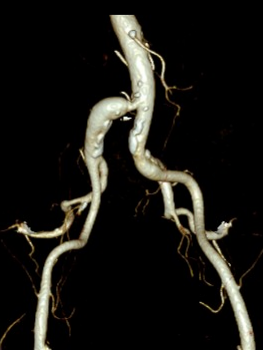

术前影像学资料:

导丝怎么扩【问术ASK】佟铸教授:双侧髂总动脉“对吻”球扩覆膜支架植入术_https://www.jmylbn.com_新闻资讯_第2张

导丝怎么扩【问术ASK】佟铸教授:双侧髂总动脉“对吻”球扩覆膜支架植入术_https://www.jmylbn.com_新闻资讯_第3张

术前ABI:左1.10 右0.62

术前诊断结果:

• 下肢动脉硬化闭塞症(R3级)

• 右侧髂总动脉狭窄

• 高血压 3级

(2)泥鳅导丝配合PIGTAIL导管进入腹主动脉,行主髂动脉造影显示:右侧髂总动脉重度狭窄,走行迂曲,后伴狭窄后扩张;双侧髂内、髂外动脉显影正常。